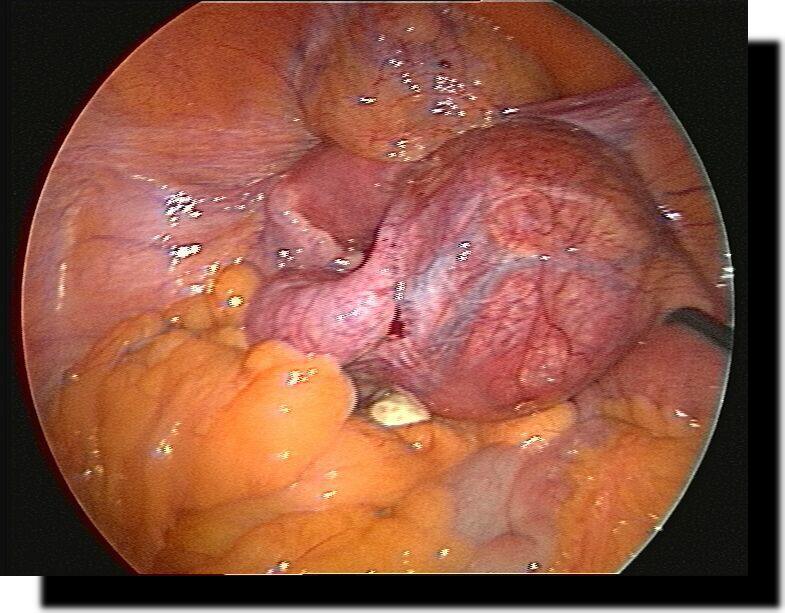

normale "unschuldige" Appendix

Akute Appendizitis

Meckel´sches Divertikel

Restappendix nach konventioneller Appendektomie

Akute eitrige Adnexitis

terminale Ileitis b. M.Crohn

Dünndarmileus durch Bride

Z.n. Bridendurchtrennung

Dünndarm-Karzinom

Dünndarmkarzinom

malignes Lymphom Dünndarm-Mesenterium

Dünndarmadhäsionen nach konventioneller Appendektomie

Sigma-Karzinom